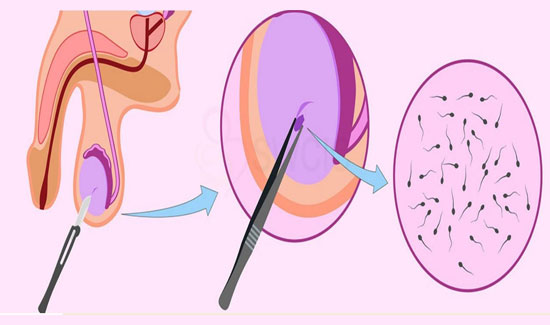

Egg Retrieval

A. Egg retrieval as a process is not a painful process as it is done under a safe and proven type of anaesthesia. However, patients might experience slight discomfort after the procedure like abdominal cramps which are taken care of by medicines.